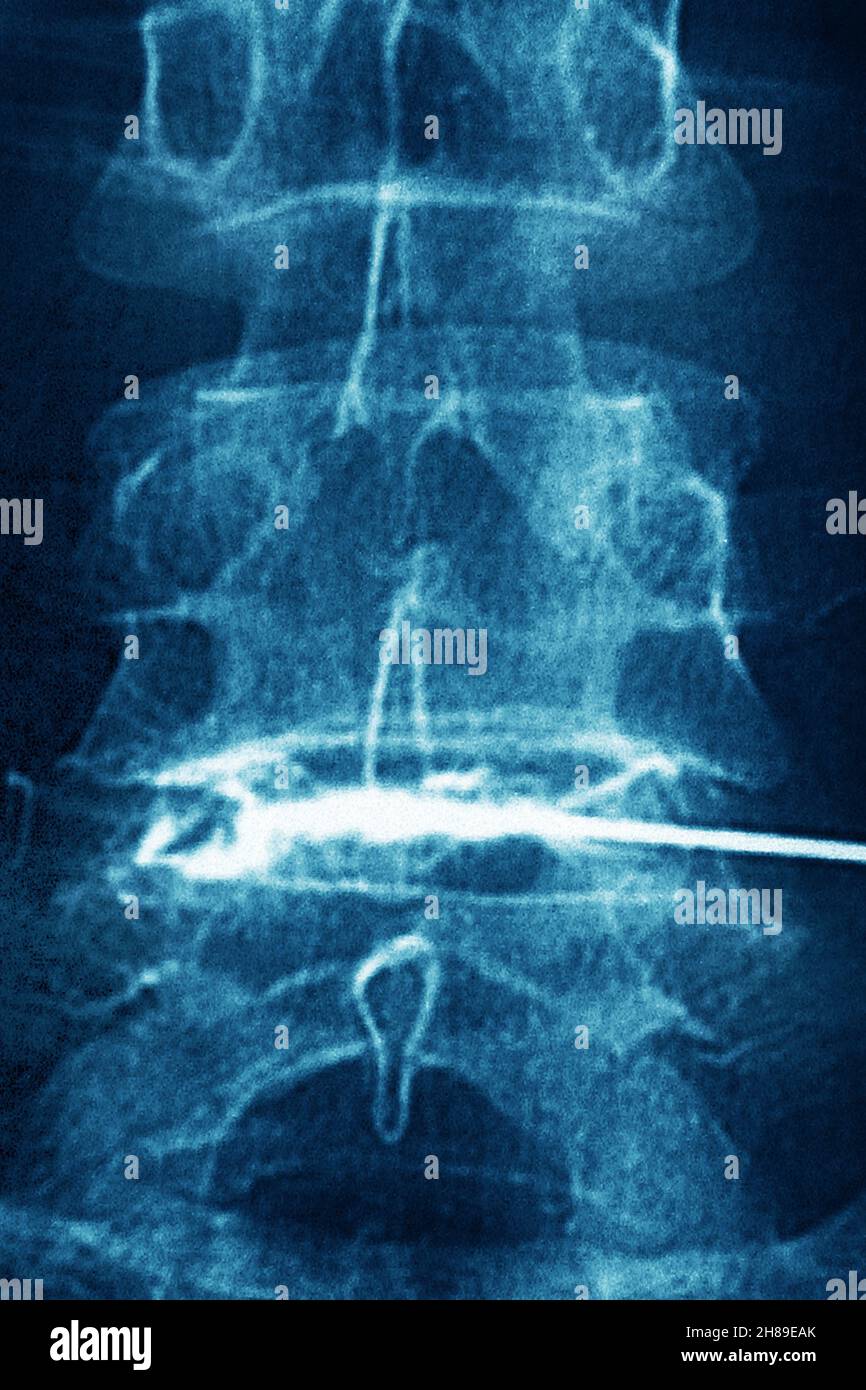

Infiltration de corticostéroïdes Banque D'Imageshttps://www.alamyimages.fr/image-license-details/?v=1https://www.alamyimages.fr/infiltration-de-corticosteroides-image452595715.html

Infiltration de corticostéroïdes Banque D'Imageshttps://www.alamyimages.fr/image-license-details/?v=1https://www.alamyimages.fr/infiltration-de-corticosteroides-image452595715.htmlRM2H89ECK–Infiltration de corticostéroïdes

Infiltration de corticostéroïdes Banque D'Imageshttps://www.alamyimages.fr/image-license-details/?v=1https://www.alamyimages.fr/infiltration-de-corticosteroides-image452595683.html

Infiltration de corticostéroïdes Banque D'Imageshttps://www.alamyimages.fr/image-license-details/?v=1https://www.alamyimages.fr/infiltration-de-corticosteroides-image452595683.htmlRM2H89EBF–Infiltration de corticostéroïdes

Infiltration de corticostéroïdes Banque D'Imageshttps://www.alamyimages.fr/image-license-details/?v=1https://www.alamyimages.fr/infiltration-de-corticosteroides-image452595703.html

Infiltration de corticostéroïdes Banque D'Imageshttps://www.alamyimages.fr/image-license-details/?v=1https://www.alamyimages.fr/infiltration-de-corticosteroides-image452595703.htmlRM2H89EC7–Infiltration de corticostéroïdes

Infiltration de corticostéroïdes Banque D'Imageshttps://www.alamyimages.fr/image-license-details/?v=1https://www.alamyimages.fr/infiltration-de-corticosteroides-image452595659.html

Infiltration de corticostéroïdes Banque D'Imageshttps://www.alamyimages.fr/image-license-details/?v=1https://www.alamyimages.fr/infiltration-de-corticosteroides-image452595659.htmlRM2H89EAK–Infiltration de corticostéroïdes